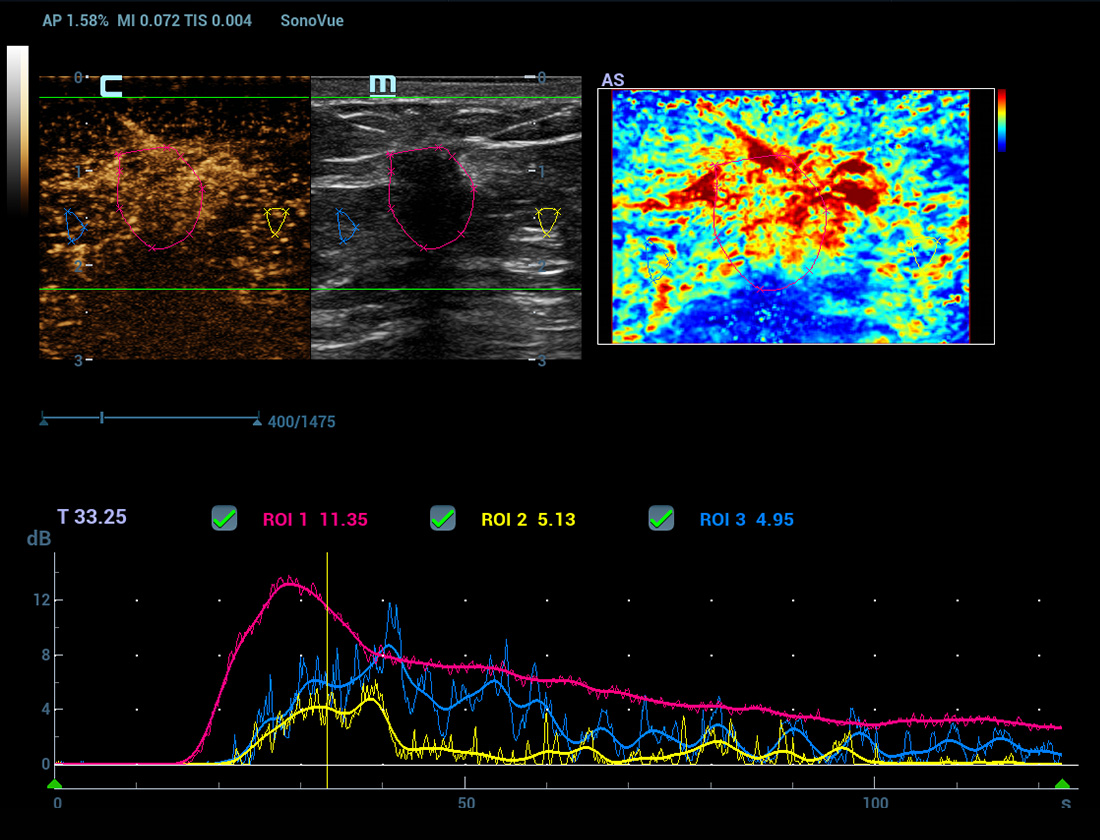

Nuova analisi quantitativa CEUS

Nuova QA CEUS tumore maligno al seno

La curva tempo-intensitĂ offre un'analisi quantitativa dell'imaging CEUS. La Nuova QA CEUS fornisce strumenti di analisi quantitativa all'avanguardia per la valutazione dei tumori e la ricerca clinica.

CEUS avanzata

CEUS UWN+(Ultra-Wideband Non-linear)

CEUS tumore maligno al seno

Utilizzando sia i segnali fondamentali di seconda armonica che quelli non lineari, UWN+ consente un'elevata sensibilitĂ ai segnali delle microbolle e una perfusione di contrasto piĂč lunga con un MI piĂč basso, per contribuire alla valutazione dei tumori.